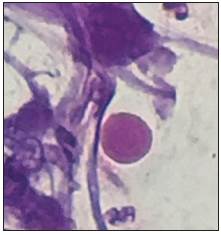

A 67-year-old male with a history of chronic obstructive pul monary disease and heavy smoking consulted due to progressive worsening of his dyspnea over the previous week along with a dry cough and unquantified fever at home. A chest x-ray showed bilateral calcified micronodules. A high-resolution computerized tomography confirmed these findings. The diagnosis was confirmed by the histological results of a bronchoalveolar lavage showing characteristic laminar microliths.

Pulmonary alveolar microlithiasis is a rare hereditary pul monary disease characterized by microcalcifications within the alveolar spaces 1. It is caused by mutations of the SCL34A2 gene which encodes the phosphate cotransporter in type II alveolar cells. This results in increased phosphate and calcium in lung surfactant, which leads to the formation and deposition of microliths within the alveoli as well as in other parts of the body 2. The definitive diagnosis requires histological identification of the microliths 3.